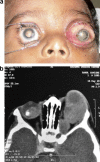

Orbital retinoblastoma is a catastrophic event traditionally carrying a dismal prognosis. Although its incidence is less in the developed countries it continues to be one of the major diagnosis at presentation in the developing world. Orbital retinoblastoma encompasses a wide range of distinct clinical entities with varying tumor load. There are no standard treatment protocols as of now but the current preferred management is multimodal with a combination of initial high-dose chemotherapy, surgery, external beam radiotherapy and prolonged chemotherapy for twelve cycles. In spite of progress on all fronts including surgical, medical, diagnostic, genetic and rehabilitative with improving survival rates, however, lack of access to medical facilities, lack of education about the need for early medical attention and cultural resistance to enucleation continue to contribute to an epidemic of extra ocular disease at diagnosis in the developing world. This review introduces the various terminologies used in the spectrum of orbital retinoblastoma, discusses in details the clinical aspects and management protocols, current status and the future directions.